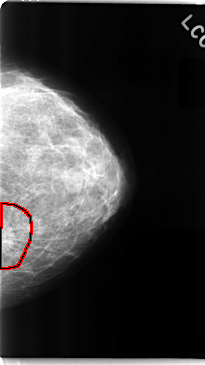

C_0091_1.LEFT_CC

LEFT_CC LINES 4744 PIXELS_PER_LINE 2664 BITS_PER_PIXEL 12 RESOLUTION 50 OVERLAY

FILE: C_0091_1.LEFT_CC.OVERLAY

TOTAL_ABNORMALITIES 1

ABNORMALITY 1

LESION_TYPE MASS SHAPE IRREGULAR MARGINS SPICULATED

ASSESSMENT 5

SUBTLETY 5

PATHOLOGY MALIGNANT

TOTAL_OUTLINES 1

BOUNDARY